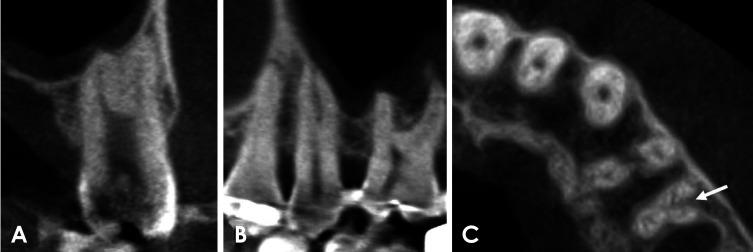

CBCT images of 585 maxillary first premolars and 578 maxillary second premolars from 303 patients were retrospectively reviewed. The number of roots was classified based on root morphology, and canal configurations were categorized into 8 types according to the Vertucci classification. For statistical analysis, chi-square or Fisher exact tests were employed to compare root number and canal morphology according to sex and tooth type.

CBCT analysis revealed that 71.5% of maxillary first premolars and 97.6% of maxillary second premolars had 1 root. The most common canal configuration in maxillary first premolars was Vertucci type IV (42.6%), whereas type I predominated in maxillary second premolars (76.5%). Significant differences in root number and canal configurations were found between men and women (<0.05), with single roots and Vertucci type I canals more commonly observed in women.

回顾性分析了303例患者的585颗上颌第一前磨牙和578颗上颌第二前磨牙的CBCT图像。根据牙根形态对牙根数量进行分类,并根据韦尔图奇分类法将根管形态分为8种类型。为进行统计分析,采用卡方检验或费舍尔精确检验来比较不同性别和牙齿类型的牙根数量及根管形态。

CBCT分析显示,71.5%的上颌第一前磨牙和97.6%的上颌第二前磨牙有1个牙根。上颌第一前磨牙最常见的根管形态是韦尔图奇IV型(占42.6%),而上颌第二前磨牙中I型占主导(占76.5%)。男性和女性在牙根数量和根管形态上存在显著差异(<0.05),女性中单根和韦尔图奇I型根管更为常见。